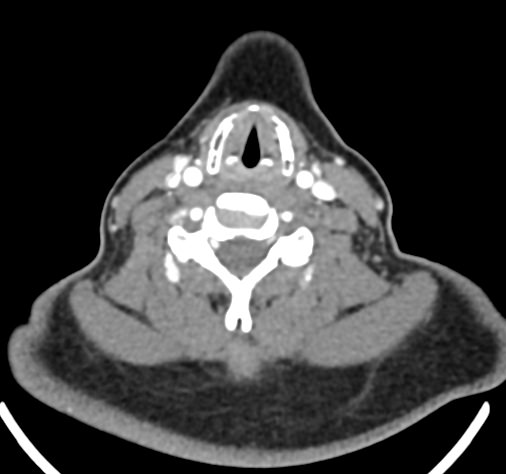

Оптимальным методом обследования гортани и голосовых связок является мультиспиральная компьютерная томография. Метод позволяет подробно визуализировать состояние данной анатомической области и выявить патологические изменения, которые незаметны при ларингоскопии (визуальный осмотр гортани с помощью специальных инструментов), проведении УЗИ и обычной рентгенографии.

Компьютерная томография позволяет оценить состояние костного скелета гортани и особенно важна в оценке состояния хрящей гортани, которые лучше всего визуализируются с помощью данного исследования. В частности, мультиспиральная КТ позволяет выявить распространение рака гортани в ткань щитовидного хряща и другие окружающие структуры.

При подозрении на опухоль гортани нативная мультиспиральная КТ дополняется проведением внутривенного болюсного контрастирования. Для этого пациенту внутривенно вводится контрастный препарат на основе йода.

Контраст хорошо накапливается в патологически измененных участках, за счет этого становятся отчетливо видны на снимках их границы, размеры, точная локализация относительно окружающих здоровых тканей. По характеру накопления контраста можно отличить доброкачественные опухоли от злокачественных, определить степень распространенности процесса, выявить поражение регионарных лимфатических узлов.

На полученных снимках можно оценить состояние всех структурных элементов гортани, голосовых складок, хрящей, а также лимфатических узлов, сосудов и шейных позвонков на исследуемом уровне. Инновационные возможности аппаратов позволяют построить 3D-модель зоны исследования, которая дает наглядную картину пространственного расположения органов, что бывает особенно важно при планировании хирургических операций.